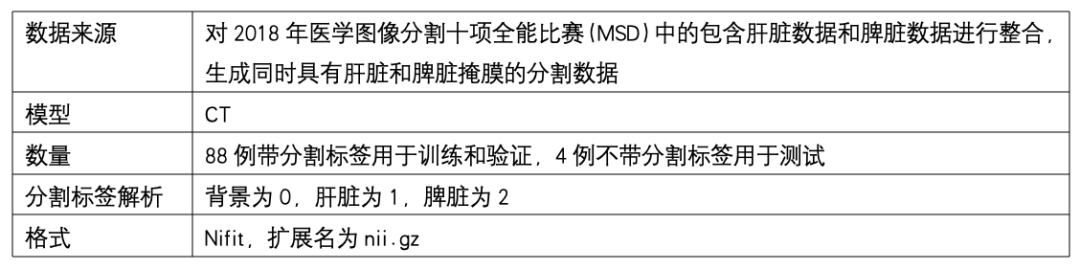

数据集介绍

用医疗软件 itk-snap 软件读取原始数据和对应分割标签,展示效果如下图: